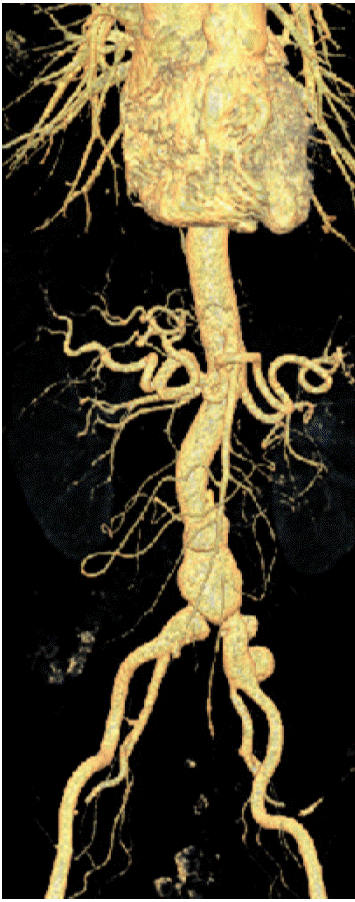

Figure 3.

Preoperative findings: The inferior mesenteric artery was divided, and diffuse swelling and inflammatory changes in the aortic wall were also noted. There was severe fibrosis and adhesion with adjacent structures, including the inferior vena cava, ureter, and iliac vein.

Figure 4.

Postoperative findings: The aneurysm and inflammatory tissue were resected. A Y-shaped PTFE graft was used to create anastomoses to the infrarenal aorta, the right external iliac artery, and the left superficial femoral artery. The right internal iliac artery was re-implanted to the graft. PTFE, polytetrafluoroethylene.